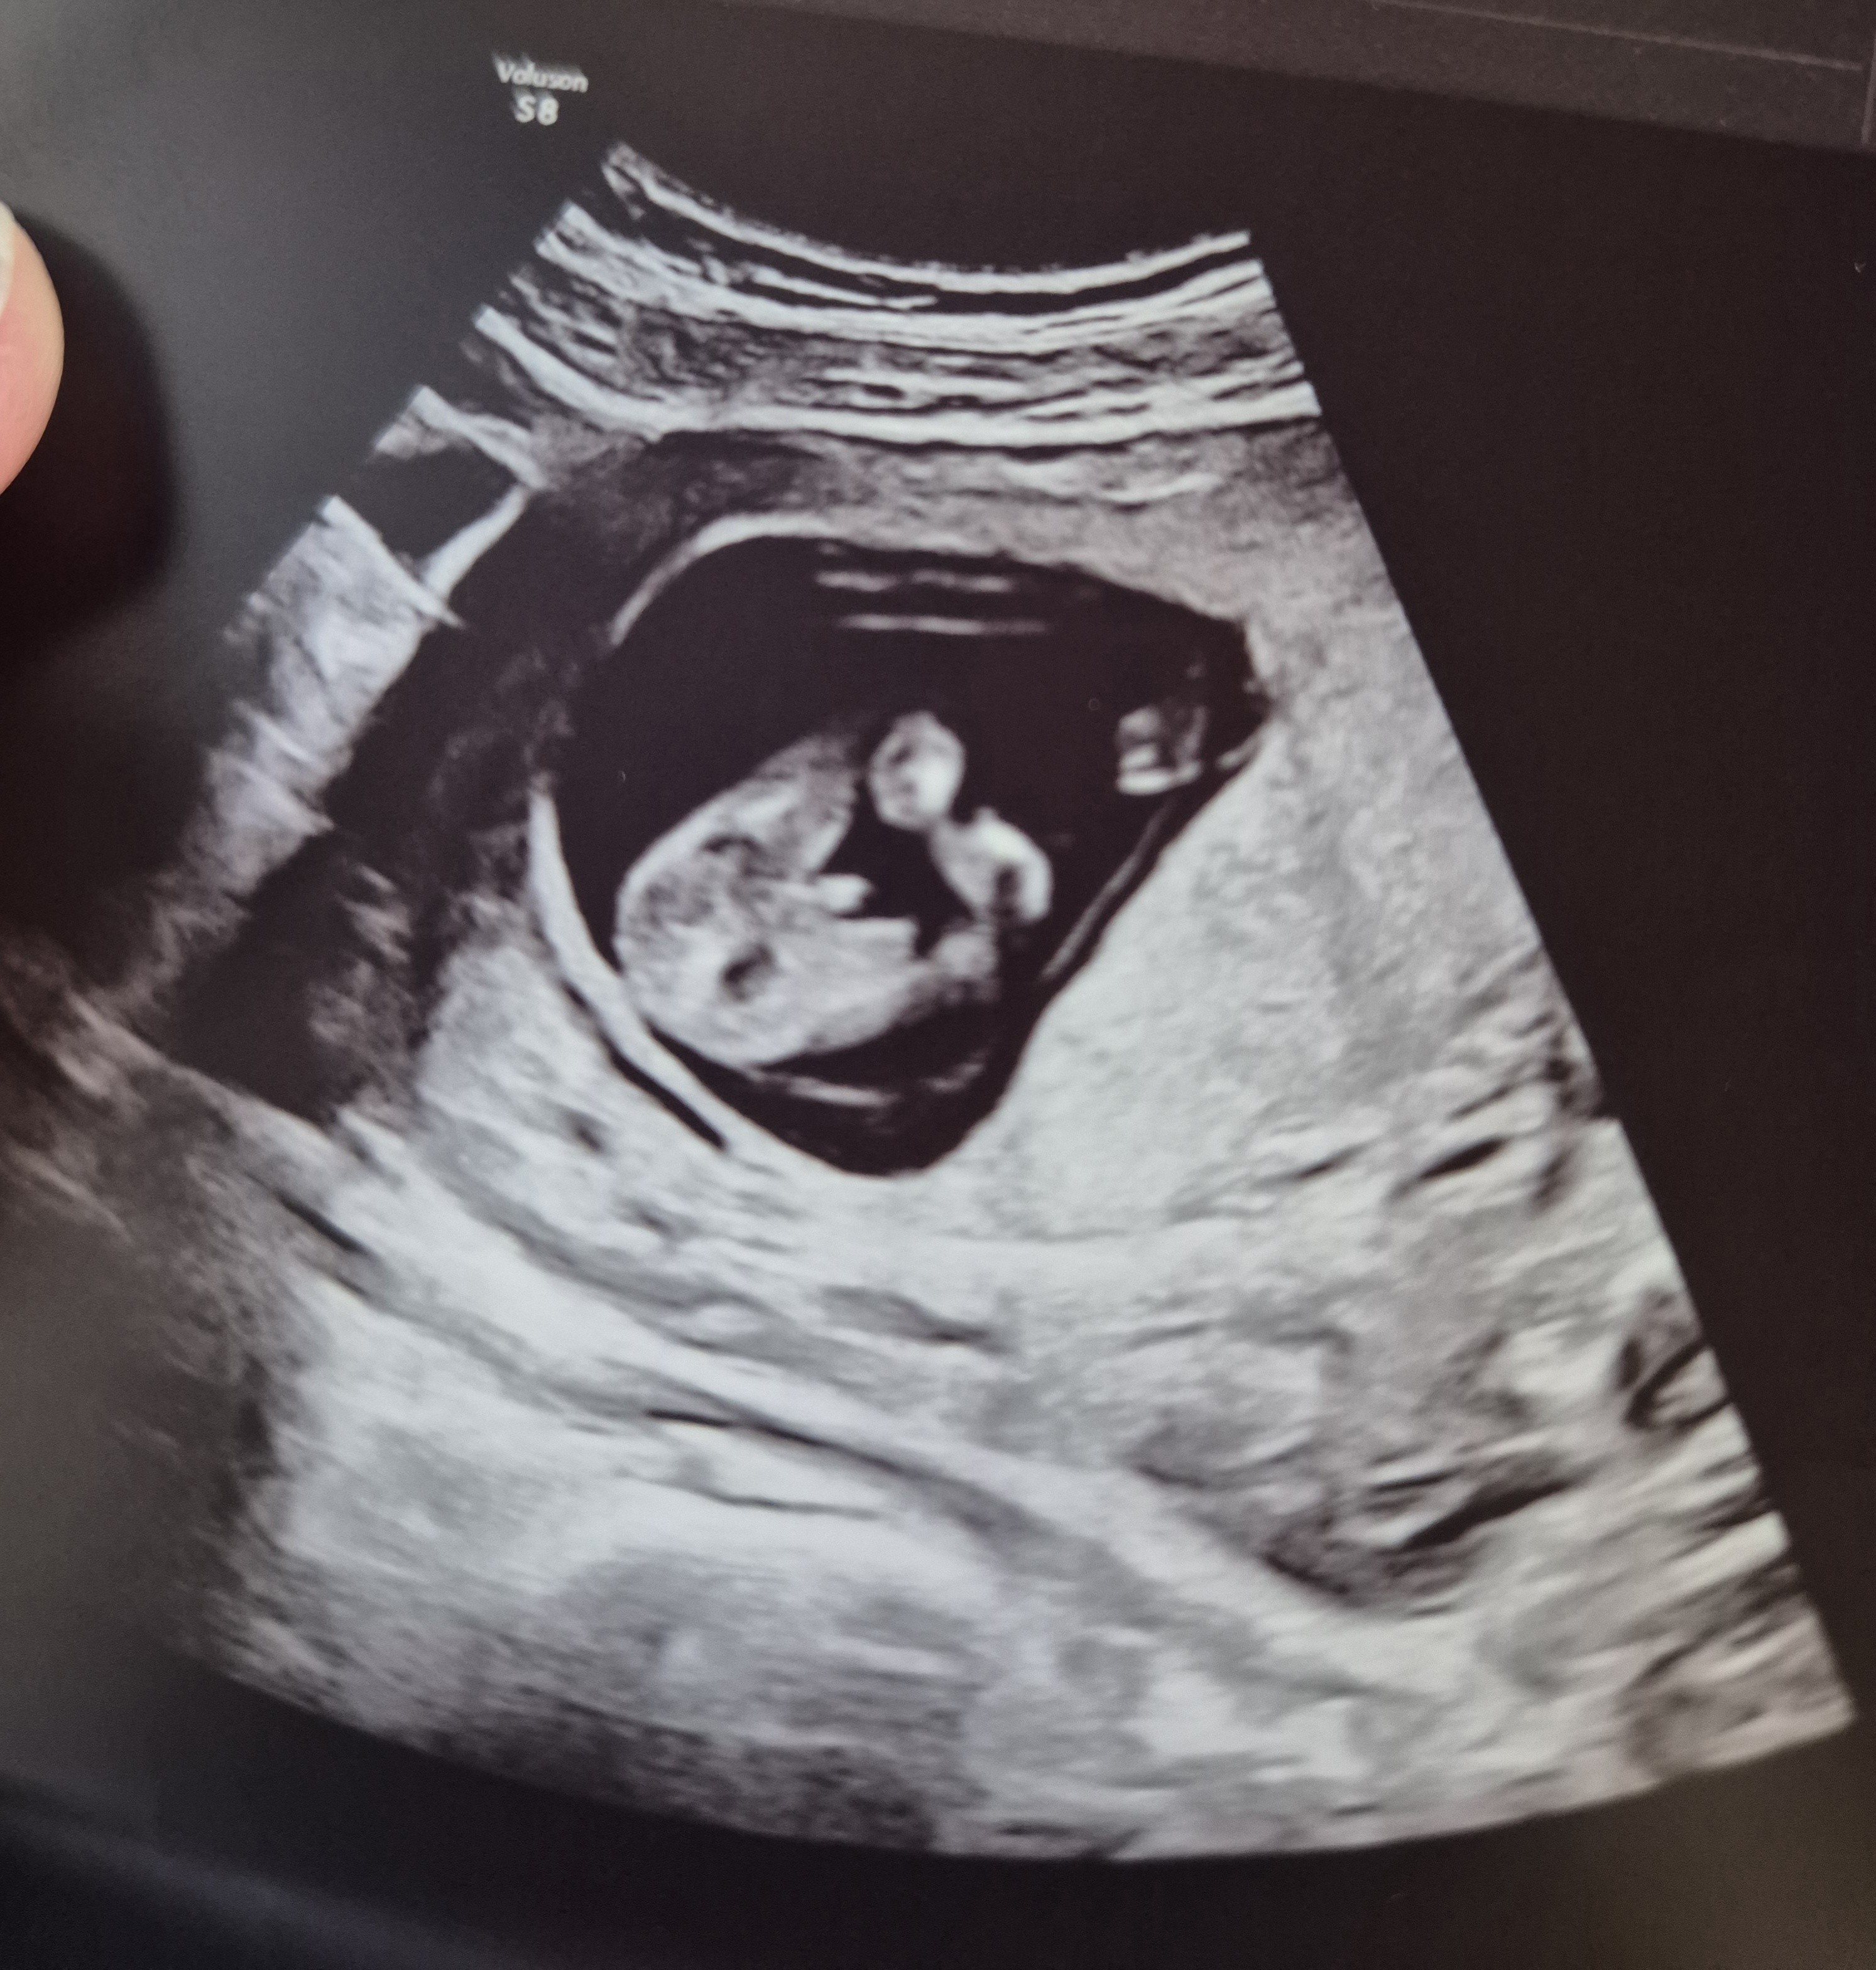

U mnie namieszali, najpierw chłopiec, teraz, że być może jednak dziewczynka. Ciężko jest się przygotować jakkolwiek. Wstawiam zdjęcie od spodu maleństwa. Możecie obstawiać, może ktoś miał podobną sytuację i ma też takie doświadczenie? Chciałabym wiedzieć kim jest mój skarb bo nie wiem jak do niego się odzywać![]()